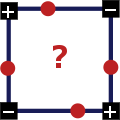

3. Два квадрата одного знака и два противоположного, квадраты с одинаковыми знаками размещены по разные стороны:

Это является исключительным случаем, чтобы принять решение берется среднее значение интенсивности во всех четырех квадратах, и если оно больше или равно порогу, то центр положителен, в остальных случаях — отрицателен. Также важно какой узел является текущим в данный момент: